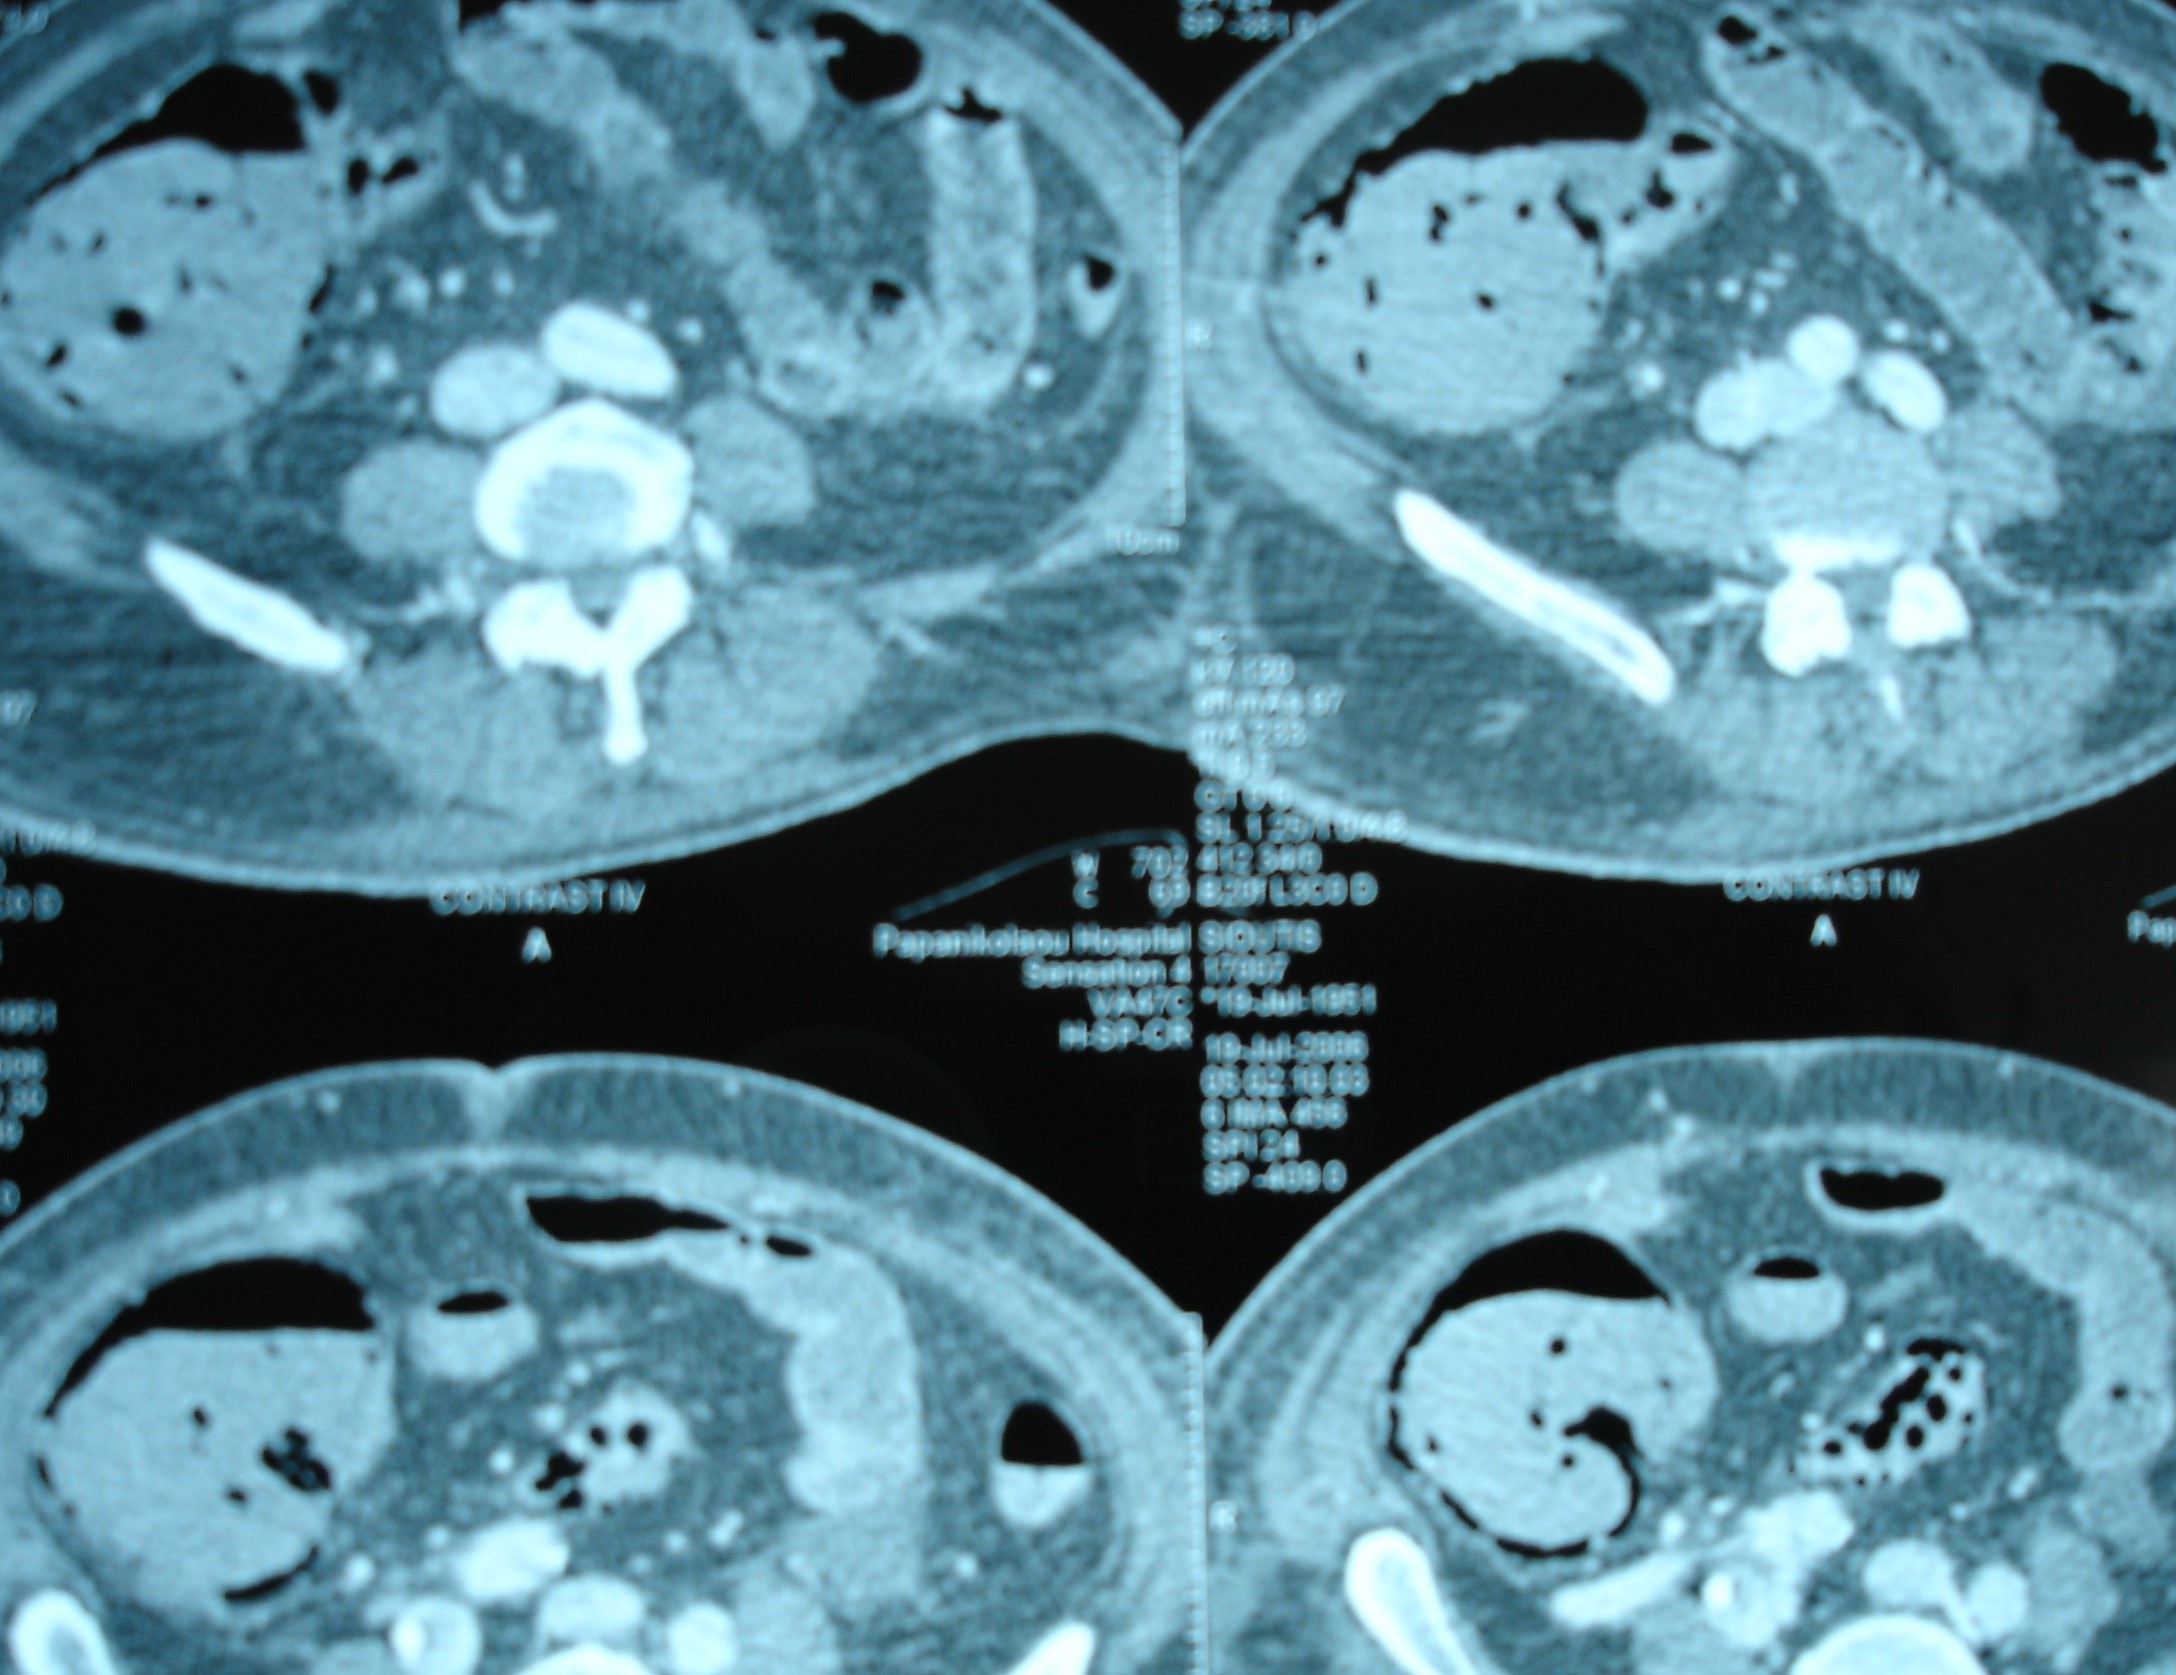

Multiple hepatic metastases — Absolute contraindication for cytoreductive surgery (Courtesy Dr. V. Penopoulos)